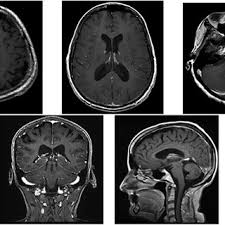

Magnetic resonance imaging MRI scan. As a result leptomeningeal disease has a poor prognosis with survival typically measured in months. Lymphomatous meningitis has a better outlook with a median survival of more than 6 months but diagnosis may be.

Leptomeningeal Metastases Radiology Reference Article Radiopaedia Org